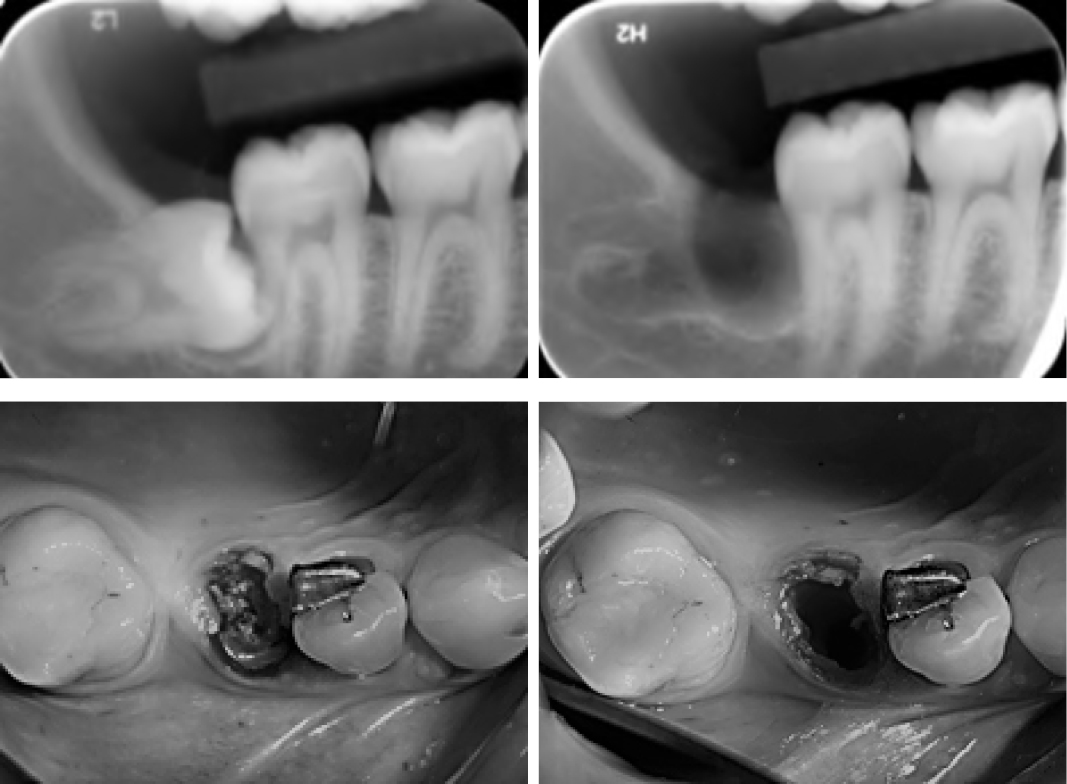

Easyroot is the solution to more conservative and atrumatic dentistry, using the new Magneto-dynamic technology. It is a big step forward compared to manual instruments .

It moves, replaces, re-shapes and condenses the bone. It never removes the bone, leaving soft tissues untouched.